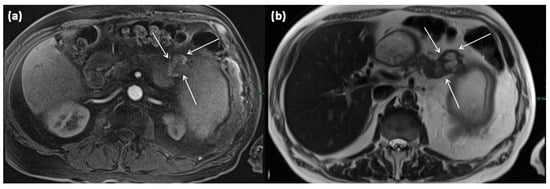

Figure 16.

MRI of a 60-year-old patient with a partly cystic and partly solid mass of the pancreatic tail. Arterial T1w after gadolinium-based contrast administration (a) typical peripheral hyperarterilization (arrows) can be seen. In T2w, solid as well as cystic parts are present (b).